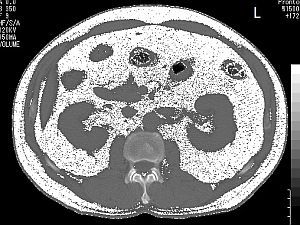

- 当院のCTで、皮下脂肪型肥満、内臓脂肪型肥満の診断ができます

下図はその実例です

| 皮下脂肪型肥満 | 内臓脂肪型肥満 |

- 内臓脂肪(白い部分)の面積100平方cm以上が、

メタボリックシンドロームの診断基準です